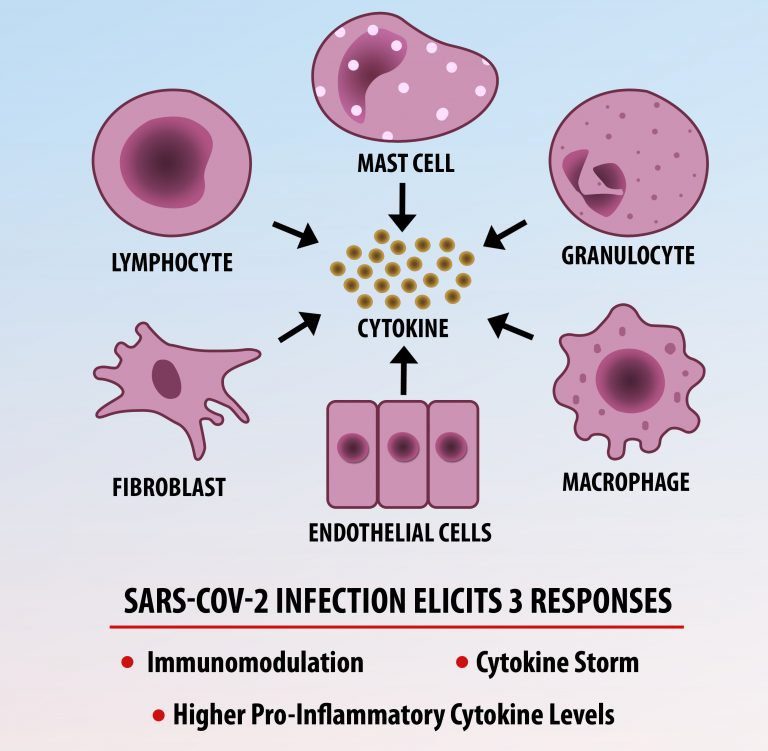

Cytokine Storm Syndrome (CSS) is characterized by systemic symptoms and signs derived from a massive and uncontrolled inflammatory response caused by pro- and anti-inflammatory cytokine dysregulation. Viruses, such as Herpes and Epstein-Barr are known to trigger CSS, as is H5N1 influenza. Current literature indicates that SARS-CoV-2 triggers CSS and has been attributed to the severe symptoms’ characteristic of critical patients. CSS in these patients is often fatal, as was the case in the previous SARS and MERS outbreaks.

The first cytokines released are interleukin 1β (IL-1β) and tumor necrosis factor-α (TNF-α), which attract a variety of circulating white blood cells (WBCs) to the infection site, including neutrophils, monocytes, macrophages, and natural killer (NK) cells. This response, along with the antipathogenic chemicals released by these cells (i.e., complement), comprise the innate immune response. These cells directly attack the invading pathogen and also release additional cytokines, chief among them interleukin-1 and 6 (IL-6). IL-6 is essential for invoking the adaptive immune response, which calls T-cells, B-cells, and T helper (Th) cells to the infection site. IL-6 also stimulates further recruitment, proliferation and activation of macrophages.

It is the ICU physician who is most likely to witness one of the deadliest manifestations of the abnormal immunological response, the cytokine storm syndrome (CSS). This response is also referred to by some as the cytokine release syndrome (CRS). CSS is characterized by continuous activation and expansion of macrophage and lymphocyte populations, which secrete large amounts of cytokines, causing the cytokine storm. This massive cytokine release is akin to hemophagocytic lymphohistiocytosis (HLH) disease, a syndrome characterized by initial unchecked and persistent activation of cytotoxic T lymphocytes and NK cells.